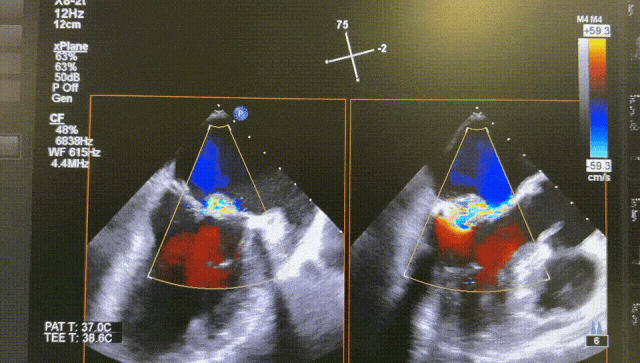

The patient was a 73-year-old male with mitral valve p2 prolapse, severe calcification of the posterior leaflet root, severe mitral regurgitation with an orifice area of 4.1 cm². After evalsuation, transcatheter mitral edge-to-edge repair (TEER) was performed using the DragonFly™ system on the patient.

The procedure was smooth and uneventful. A SW0609 mitral clip was implanted to close the leaflet at P2, and the patient's regurgitation disappeared, with a mitral pressure difference of 2 mmHg and a significant decrease in left atrial pressure.

Before

After